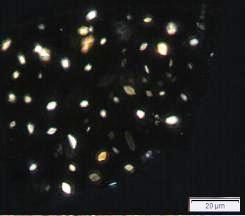

Thin Layer Chromatography (TLC)

Figure 3: TLC chromatogram of catechin (S) and methanol extract of A. bilimbi dried fruit powder (L) observed under (a) UV at visible light after derivatisation, and (b) UV at 366 nm after derivatisation.

| Test Solutions | Weigh about 4.0 g of A. bilimbi dried fruit powder of 0.355 mm size in a 50 mL round bottom flask. Add 20 mL of methanol and shake gently for 1 min and then, reflux for next 20 min. Turn off the reflux and allow to cool at room temperature. Filter the mixture with filter paper into round bottom flask. Use the filtrate as test solution. |

| Standard solution | Dissolve catechin standard [CAS no.: 225937-10-0] in methanol to produce a standard concentration of 0.1 mg/mL. |

| Stationary Phase | HPTLC glass silica gel 60 F254, 10 x 10 cm |

| Mobile phase | Toluene : ethyl acetate : formic acid; (5 : 4 : 1) (v/v/v) |

| Application |

| Development distance | 8 cm |

| Drying | Air drying |

| Detection |

UV at 366 nm and visible light after derivatisation with 1% methanolic solution of natural product reagent and heat at 105˚C for 5 min. |